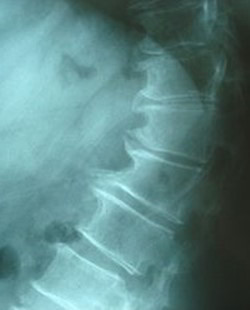

Spondylosis is osteoarthritis changing the spinal column where the vertebrae and the disks of cartilage between them start to degenerate. Where motion is best, that’s in the neck and the lower back, the bones become thickened, and bony spurs called osteophytes grow on the borders of the vertebrae. Osteophytes may press on spinal nerves, giving rise to root pain radiating down the arms and legs.

As spondylosis may be symptomless, the illness is often just diagnosed when an X ray is taken for another reason.

- If you experience neck pain or dizziness, you should consult your physician, who may organize X rays to try to find indications of cervical spondylosis.

- CT (computerized tomography) scan or MRI (magnetic resonance imaging) might also be carried out to see whether there have been any changes in the bones of the spine, the disks or cartilage between them, or the tissues around them.